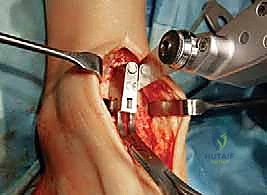

تُجرى العملية عادة تحت التخدير العام أو التخدير النصفي (الشوكي). يقوم د. هطيف بعمل شق جراحي أمامي أو جانبي (حسب التقنية المستخدمة وحالة المريض) للوصول إلى مفصل الكاحل بعناية، مع الحفاظ على الأوتار والأعصاب والأوعية الدموية المحيطة.

3. إزالة الأسطح التالفة (تحضير العظام)

باستخدام أدوات جراحية دقيقة وموجهات خاصة، يتم إزالة الغضاريف التالفة وجزء رقيق جداً من العظام المريضة من نهايتي عظمة الظنبوب وعظمة الكاحل (Talus). يتم تشكيل العظام بدقة لتتطابق تماماً مع شكل أجزاء المفصل الصناعي.